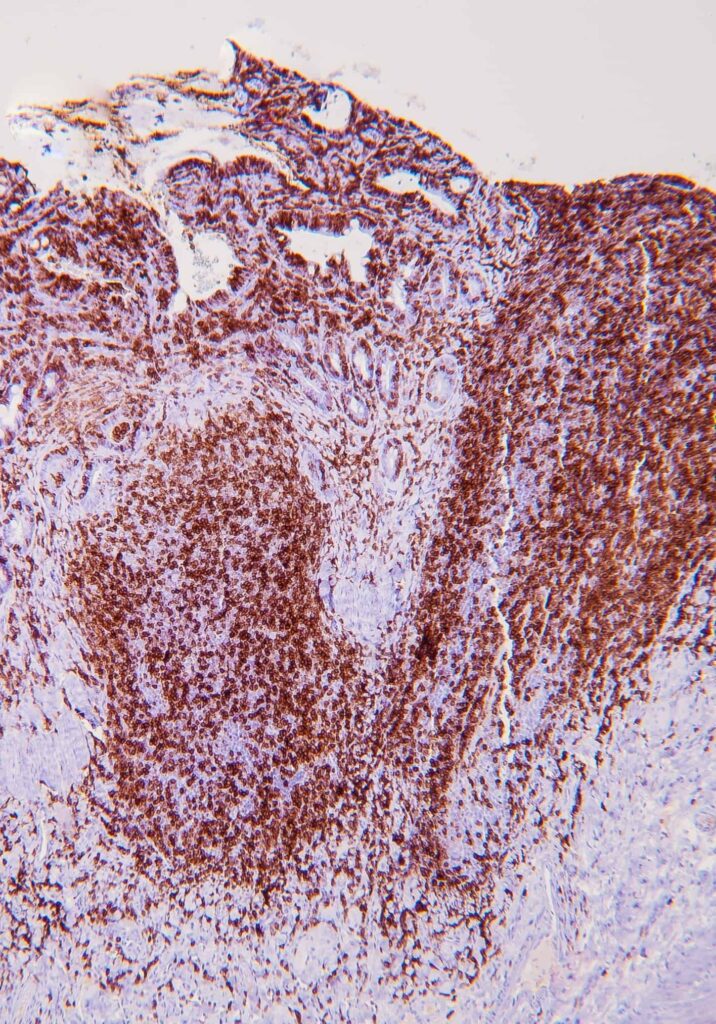

Immunohistochemistry (IHC)[GO(2]

IHC involves the use of antibodies against specific antigens in tissue sections. When lymphoma is suspected, a panel of T and B-cell antibodies (eg, CD3 and CD20) can identify a monomorphic population and establish the cell lineage. Antibodies such as Ki67, pSTAT3 and pSTAT5 have been recently studied and are useful for the diagnosis of LGTIL (Freiche et al, 2021 b).

KEY POINT: The combination of histopathology and IHC is considered the gold standard for diagnosis of LGTIL